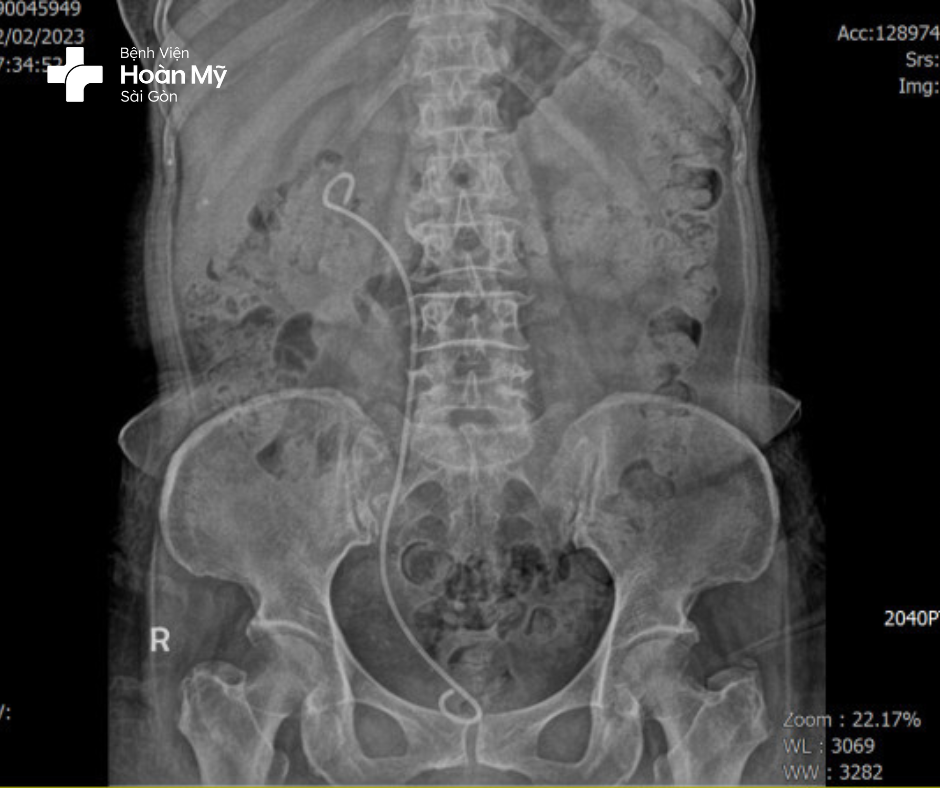

Hình 1: Sỏi niệu quản Phải, thận Phải ứ nước

Người bệnh lập tức được chuyển đến hoa Hồi sức tích cực để điều trị và được tiến hành hội chẩn toàn viện để phẫu thuật giải quyết tình trạng tắc nghẽn do sỏi bằng phương pháp đặt sonde JJ niệu quản phải.